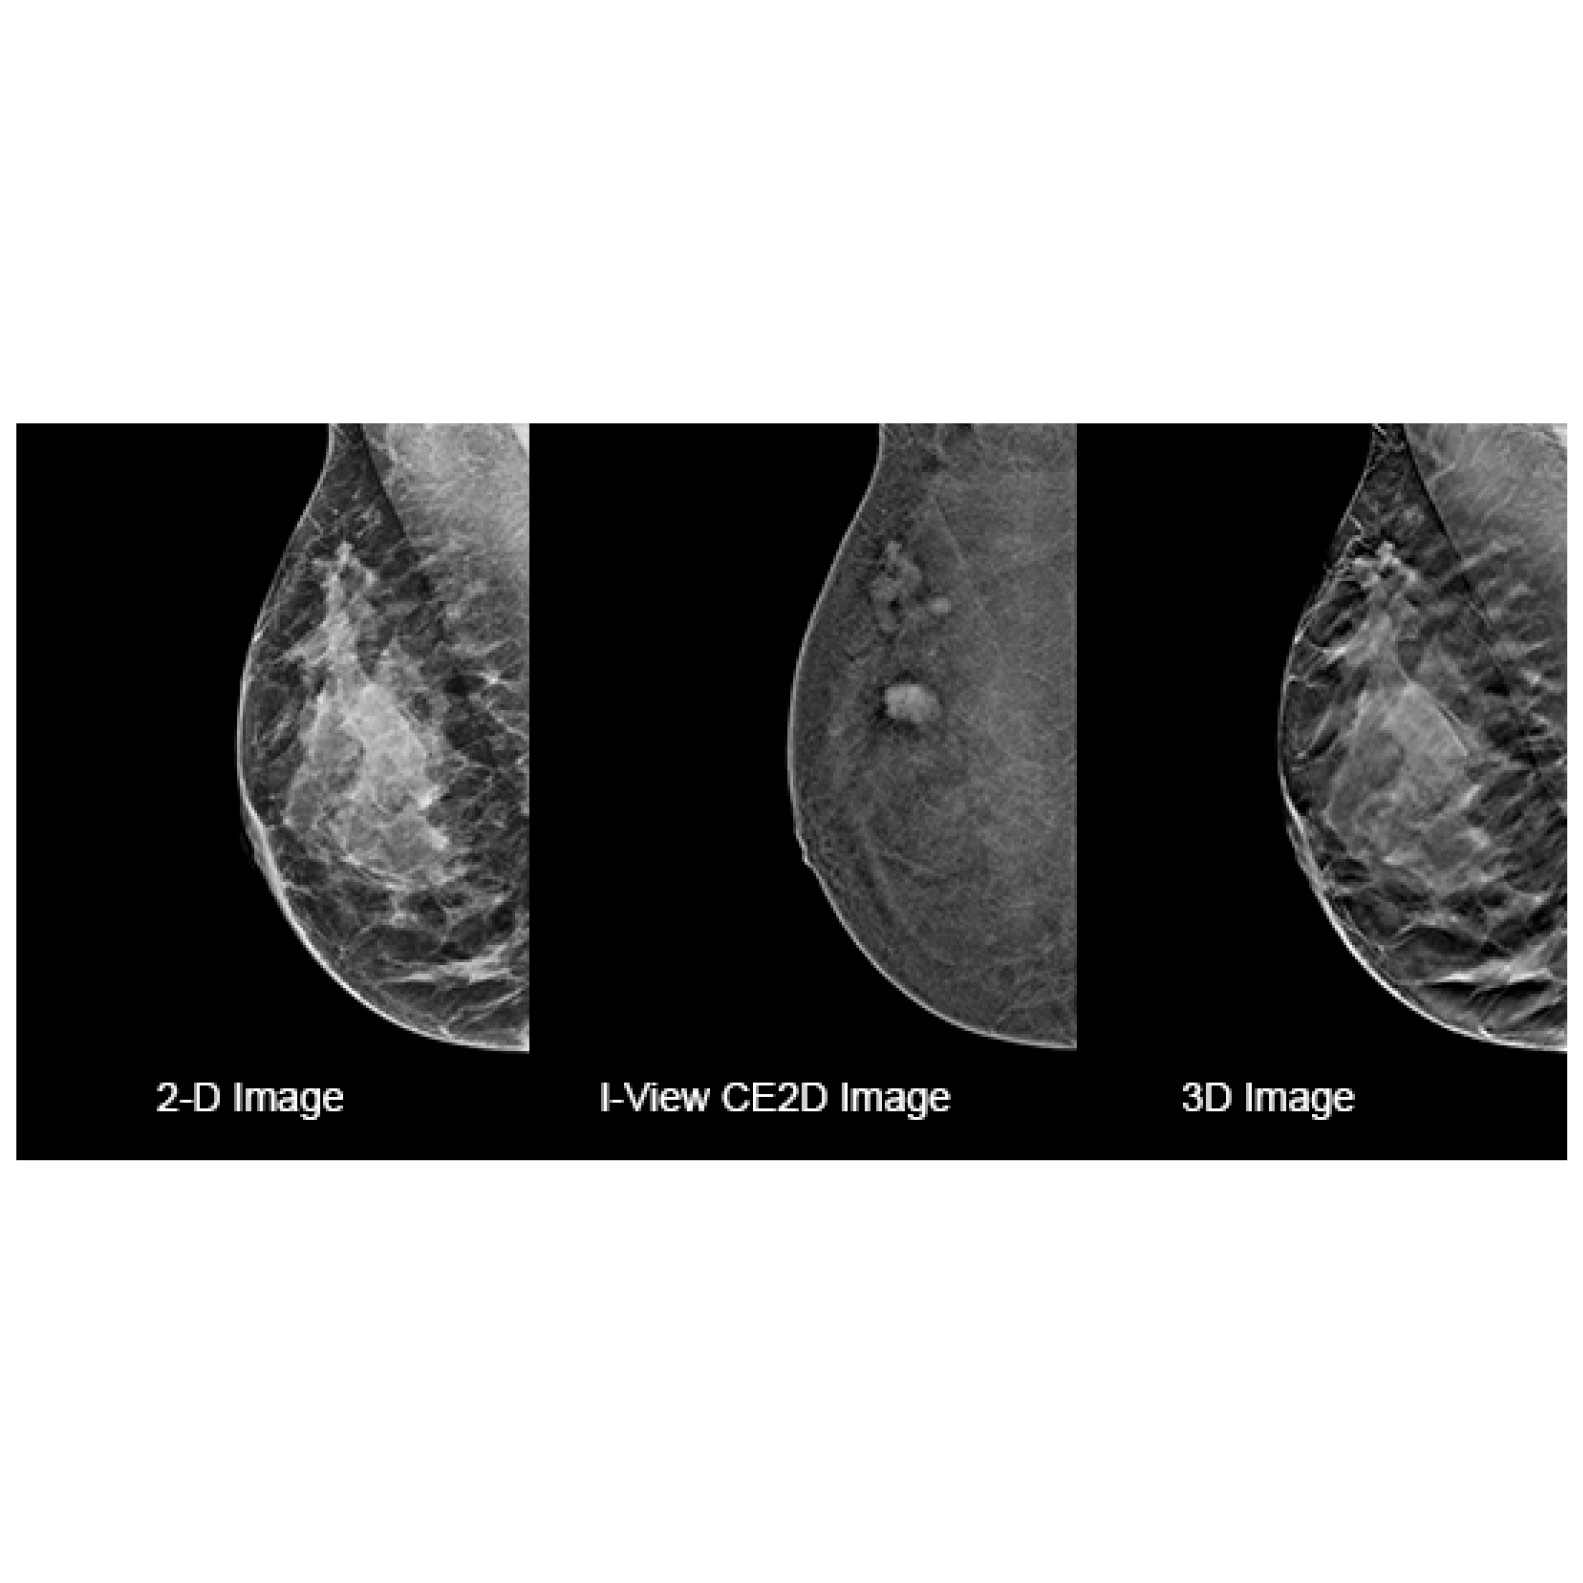

Hologic has more solutions that help radiologists identify and detect breast cancer in women with dense breasts.

Hologic and Bayer join forces to provide a coordinated Contrast-Enhanced Mammography solution